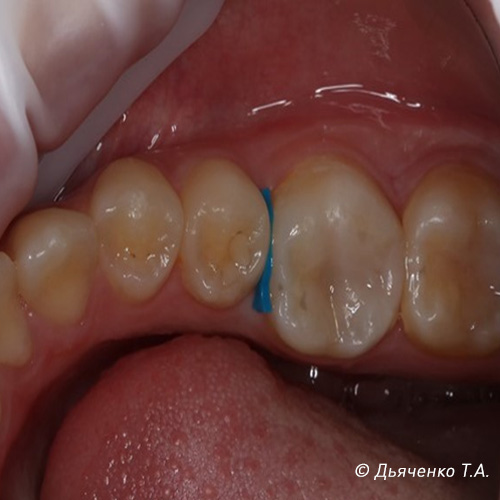

На рисунках 1 и 2 изображен межзубный, контактный кариес 26 зуба.

Процесс лечения межзубного, контактного кариеса 26 зуба показан на рисунках 3, 4 и 5.